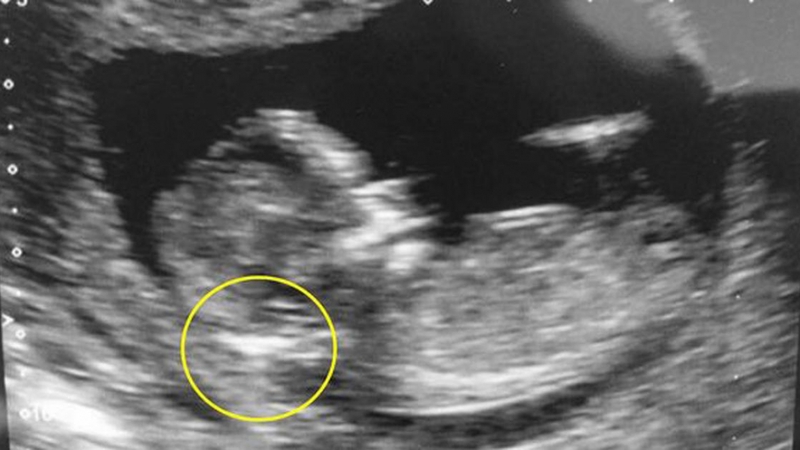

Vậy siêu âm 4D có phát hiện bệnh Down không? Theo các bác sĩ chuyên khoa sản, bệnh Down hoàn toàn có thể được phát hiện sớm thông qua siêu âm 4D đo độ mờ da gáy. Thời điểm vàng để nhận biết em bé có bị Down hay không vào khoảng tuần thứ 11 - 13 của thai kỳ. Những bé có nguy cơ cao mắc hội chứng Down thường có da gáy dày trên 2,5mm.

[Hỏi đáp] Siêu âm 4D có phát hiện bệnh Down không 1 Hình ảnh cho biết siêu âm 4D có phát hiện bệnh Down không

Độ mờ vai gáy thường là căn cứ đầu tiên giúp bác sĩ phát hiện bất thường trên thai nhi mắc hội chứng Down. Trên hình ảnh siêu âm 4D khoảng sáng sau gáy càng dày tức là nguy cơ trẻ bị Down càng cao. Tuy nhiên, độ chính xác để chẩn đoán nguy cơ thai nhi bị Down qua đo độ mờ da gáy chỉ đạt 75%. Muốn chẩn đoán chính xác hơn, bác sĩ còn căn cứ vào các biểu hiện khác trên hình ảnh siêu âm, gồm: